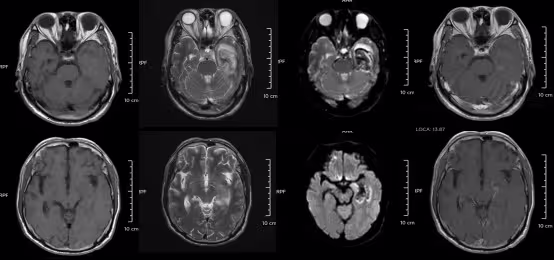

示意圖翻攝自浙江大學醫學院附屬第二醫院